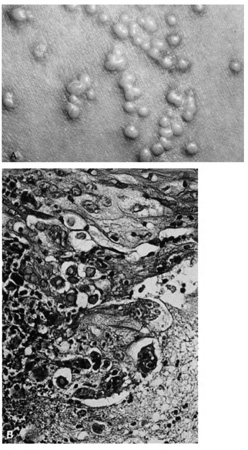

Verruca vulgaris (warts) are caused by a variety of papilloma viruses and may present as small papules with a digitated surface or elongated filiform warts around the eyes. Histologically, they demonstrate varying degrees of massive papillomatosis, hyperkeratosis, and acanthosis with parakeratosis and collections of serum in the stratum corneum at the tips of the digitations (Fig. 8). In early warts, the keratinocytes in the granular layer and just beneath the granular layer are vacuolated with condensation and clumping of dark-staining keratohyaline granules and occasional eosinophilic inclusion bodies in the nuclei.

Fig. 8. Verruca Vulgaris—A. Low-power photomicrograph illustrating papillomatous growth with a fibrovascular core, hyperkeratosis, and acanthosis (hematoxylin and eosin stain). B. High-power photomicrograph demonstrating intranuclear viral inclusion (black arrow) (hematoxylin and eosin stain). (Photos courtesy of William Morris, M.D.)